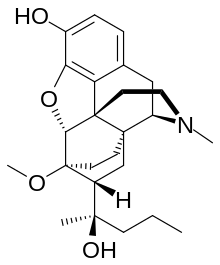

| Oripavine derivatives | ||||

|---|---|---|---|---|

7-PET 7-PET |

Acetorphine Acetorphine |

Alletorphine Alletorphine |

BU-48 BU-48 |

Buprenorphine Buprenorphine |

Cyprenorphine Cyprenorphine |

Dihydroetorphine Dihydroetorphine |

Etorphine Etorphine |

Homprenorphine Homprenorphine |

18,19-Dehydrobuprenorphine 18,19-Dehydrobuprenorphine |

N-cyclopropylmethylnoretorphine N-cyclopropylmethylnoretorphine |

Nepenthone Nepenthone |

Norbuprenorphine Norbuprenorphine |

Thevinone Thevinone |

Thienorphine Thienorphine |